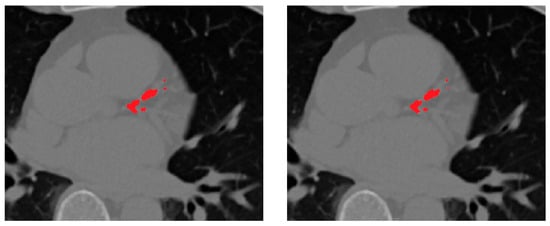

The vesselness-enhanced inputs allow the ASOCA-trained ResU-Net to delineate coronary arteries more accurately, even in regions with low contrast-to-noise ratio. When applied to the gated COCA CT scans—cropped to the heart ROI—the resulting vessel masks serve as anatomical constraints for the downstream calcification segmentation stage. These vessel priors ensure that detected lesions are spatially restricted to plausible coronary regions, reducing false positives near the aorta, valves, or pericardium and improving the sensitivity and specificity of calcification segmentation. Examples of the heart and coronary arteries segmentations are shown in Figure 4.

Figure 4. Heart and Coronary Vessel Segmentation: original CT slice, predicted heart region of interest (ROI) and 3D coronary artery segmentations.